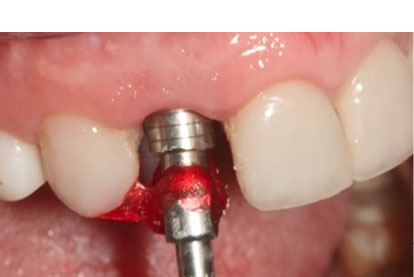

A temporary cylindrical abutment was tightened on the implant, and a composite-based provisional crown (Dentocrown, Itena, Villepinte, France) was fabricated on the temporary cylinder to make a screw-retained provisional restoration (Figure 5B). The occlusal assessment was made, and any centric and eccentric contacts were eliminated. Amoxicillin, 500 mg (q8h for seven days), gelofen, 400 mg (q6h for seven days), and 0.2% CHX mouthwash (twice daily for a week) were prescribed. The patient was placed on a soft diet for two months.

Figure 5.

(A) Placement of an Osseotite implant in the extraction socket. Immediate provisional composite-based crown from the frontal (B) and occlusal views (C)